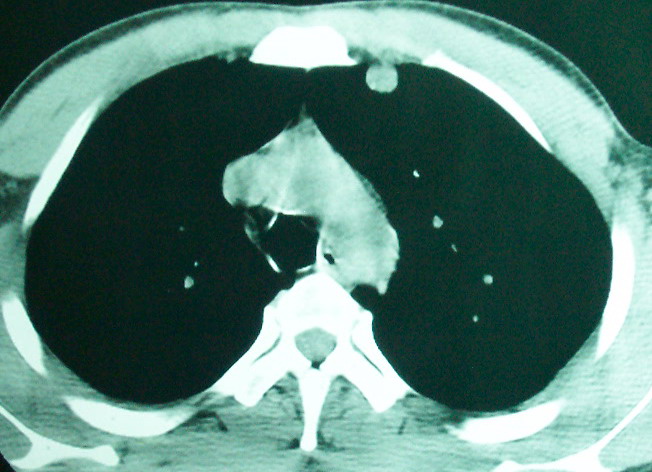

m      37y      发热   咳脓痰月余      ct肺脓肿但住院抗炎治疗后双肺内结节不知该如何解释

治疗后见左肺下野病灶较前缩小但双肺内结节影似无变化请较各位老师该如何下结论    治疗前wbc14.5 治疗后wbc 11.0

空洞内可见小结节样密度影考虑合并真菌感染

左下肺病灶除了明显的厚壁空洞 气液平外,明显见壁结节,另两肺多发小结节,综合考虑:左下肺周围性肺癌伴肺内转移.

鳞癌肺肺转移:厚壁空洞,洞壁厚薄不均,内似有壁结节,肺脓肿临床有无提示,血像如何?病灶周围很干净,没有明显渗出,很勉强?

如果你仔细的同层面对比,你会发现所有的病灶均有比较明显的吸收、缩小。病变的形态,特别是脓肿的形态、壁的厚薄、内壁均有很大的变化,均在往好的方面发展。与临床症状、血像均符合,治疗效果比较显著,就是肺脓肿并双肺的化脓性炎症灶。